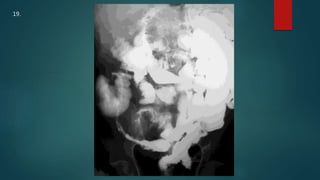

This document appears to be a medical report discussing several patients. It mentions a 35-year-old who was in a severe motor vehicle accident and an 81-year-old with a history of a non-vegetarian diet who had a perforated bowel from a chicken bone. The document provides few other details across its 25 numbered entries and was authored by Dr. Anish Choudhary for junior year 3 on May 30, 2016.